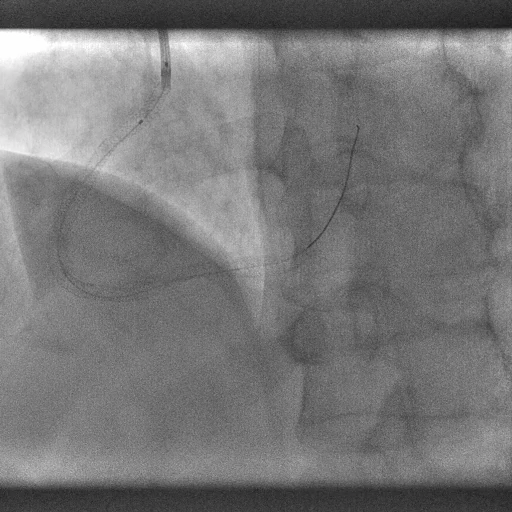

开通后,粗大的右冠状动脉血管显示出来,患者心脏缺血明显改善,心脏“发动机”再次满血运作,图为再次满血运作的血管